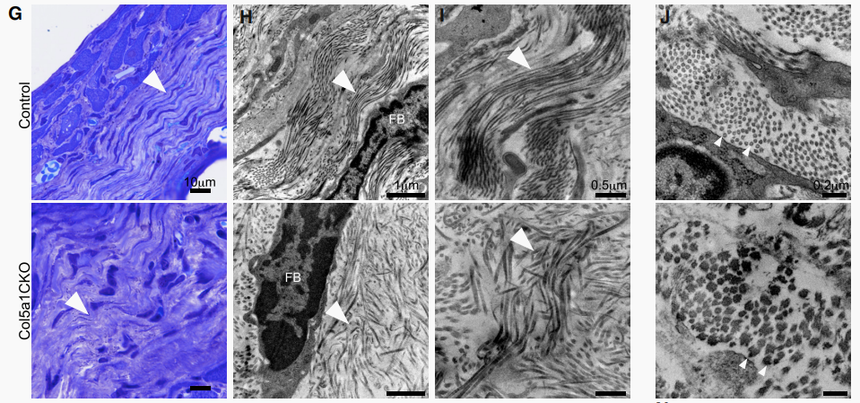

瘢痕組織甲苯胺藍(lán)染色和透射電鏡檢測(cè).png

瘢痕組織甲苯胺藍(lán)染色和透射電鏡檢測(cè)